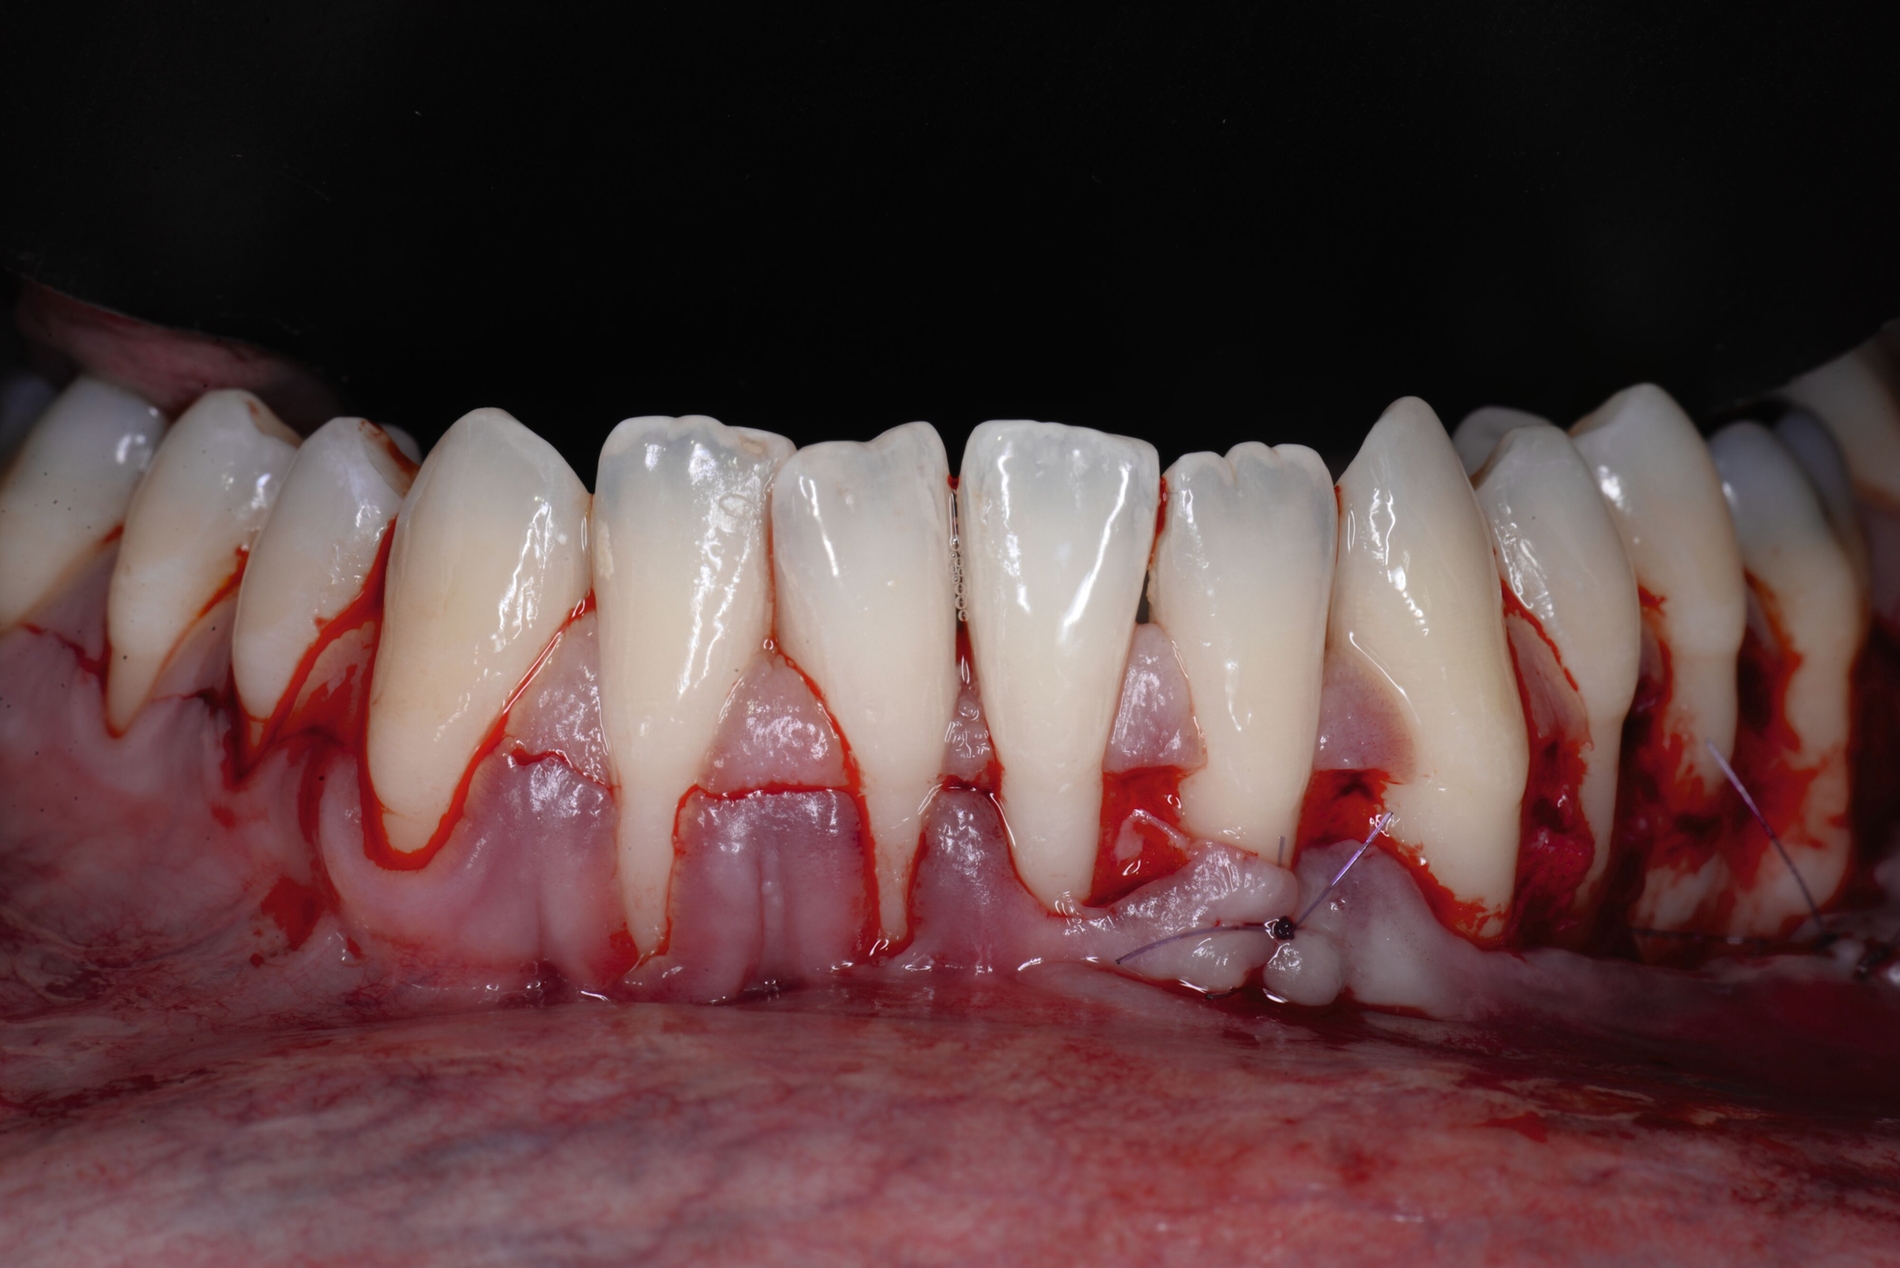

Beim lateralen Verschluss der tiefen Rezession im Rahmen der LCAT- oder LCAF-Technik ist immer mit dem Auftreten von Spannungen zu rechnen, insbesondere wenn die Rezession eine deutliche Breite aufweist. Nicht möglich ist dieses entlastungsinzisionsfreie Vorgehen, wenn mehrere tiefe Rezessionen direkt oder unmittelbar benachbart sind, da dann das Gewebe in die entgegengesetzte Richtung lateral mobilisiert werden müsste. Für diese Patienten haben Tunkel et al. eine Methode entwickelt, die grundsätzlich die Prinzipien der Koronalverschiebung nach Zucchelli, die Nelson-Technik und die LCAF-Technik verbindet und versucht, deren Vorteile zu kombinieren und deren Nachteile zu kompensieren: den „Mehrfach Gestielten Koronal Verschobenen Lappen“ (MPCAF) [Tunkel et al., 2021; Tunkel et al., 2022] (Abbildung 4). Gleichzeitig ist es damit möglich, mehrere auch direkt nebeneinander liegende Rezessionen zu decken.

Dabei wird zunächst – wie bei der LCAF-Technik – die Gingiva der tiefen Rezessionsareale exzidiert und die Inzision in gleicher Weise horizontal erweitert (Abbildung 4b). Zum Ende des gewünschten Präparationsareals wird aber eine vertikale Entlastungsinzision gezogen. Hier gibt es aber deutliche Unterschiede zur Nelson-Technik: Die Inzision liegt durch die horizontale Erweiterung weiter von der tiefsten freiliegenden Wurzeloberfläche entfernt und wird bei multiplen Rezessionen auch möglichst in den Seitenzahnbereich verlegt, damit die daraus resultierenden Narben später nicht sichtbar werden. Zudem wird die Rezession nicht gerade, sondern in einem runden Rückschnitt geführt, so dass zur Lateralisation keine Verschiebung, sondern eine Rotation durchgeführt werden kann, was trotz der seitlichen Verlagerung eine Deckung des Areals der Entlastungsinzision ermöglicht.

Jetzt wird beginnend an einer Seite der erste Lappenanteil nach dem Prinzip teilschichtig-vollschichtig-teilschichtig gelöst und im Bereich der ersten tiefen Rezession mittels feiner monofiler Nähte mit dem proximalen Lappenanteil vernäht. Dieser wird daraufhin gelöst und bei der nächsten tiefen Rezession erneut mit dem nahe gelegenen Lappenanteil verbunden. Dieser Vorgang wird fortgeführt, bis so erneut ein großer gesamter Lappen entstanden ist, der koronal verschoben werden kann (Abbildung 4c). Das weitere Vorgehen ist exakt wie bei der LCAF-Technik: Entepithelialisierung der Papillenareale, Gewinnung des Transplantats, Applikation von EDTA-Gel und Schmelz-Matrix-Proteinen, Fixation des Transplantats und Fixierung des Lappens nach koronal (Abbildungen 4d bis 4f). Die runden Entlastungsinzisionen lassen sich meist ohne größere Mühe verschließen, selbst wenn multiple tiefe Rezessionen vernäht worden sind.